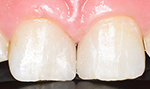

症例2(すきっ歯)

50代の患者さんで前歯の隙間に物が挟まったり空気が漏れる感じがすると訴えておりました。

隙間を埋めてから悩みが解消しましたと喜んでおられました。

回数2回 費用6,0000円

術前

術後